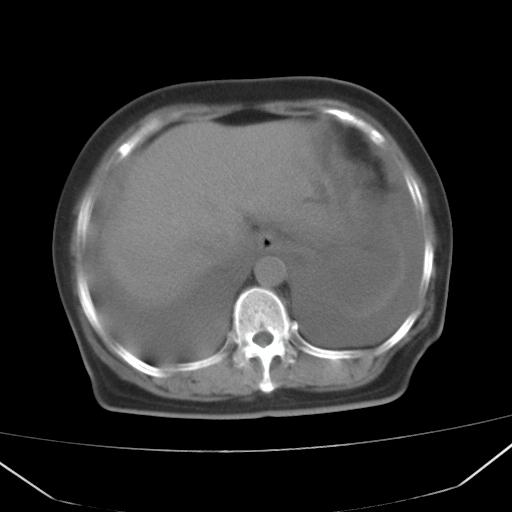

以下是引用jiangjing在2008-4-20 10:43:00的发言:[br]结合病史支持 冠心病[冠状动脉钙化],心功能不全,肺淤血、肺水肿,双侧胸腔与斜裂积液

以下是引用liuyue在2008-4-19 22:25:00的发言:[br]先考虑:1.心衰伴肺水肿、双侧胸腔积液、叶间积液、双下肺不完全性肺不张; [br] 2.冠状动脉粥样硬化。

以下是引用lijuanln在2008-4-19 23:05:00的发言:[br]两侧胸腔积液,肺水肿[br]心包积液[br]提示心衰